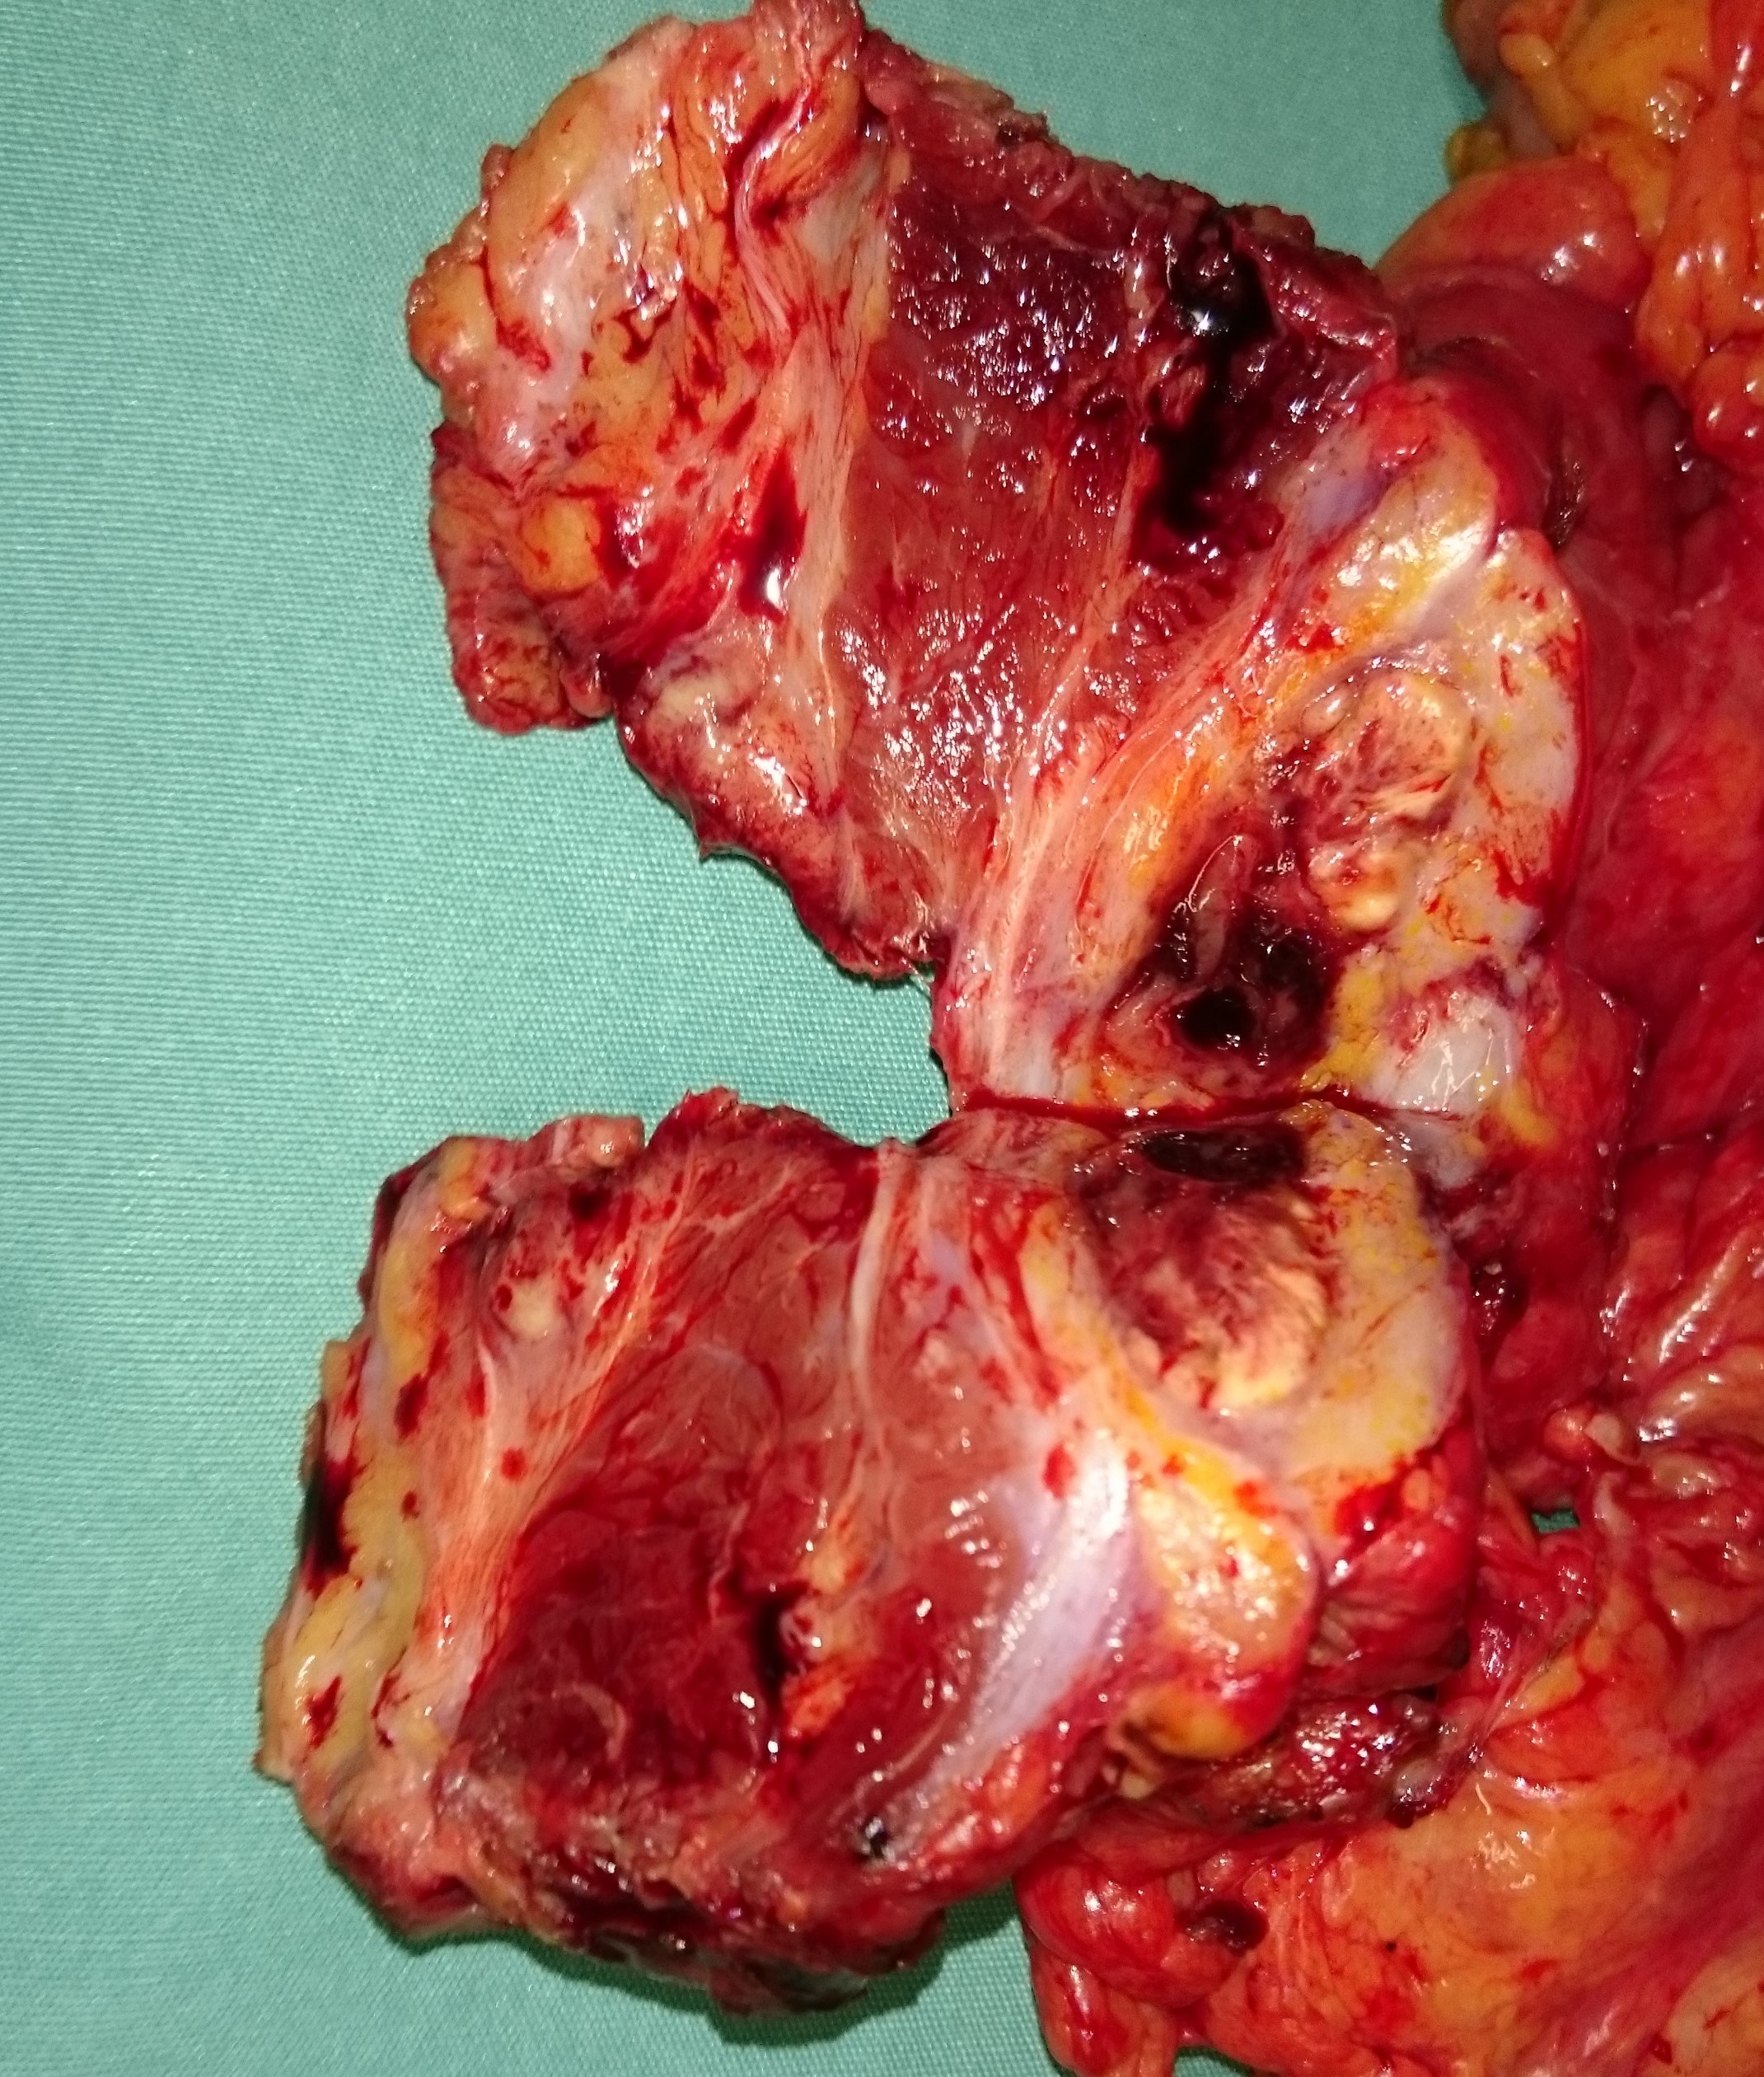

Εκτεταμένη κολεκτομή ισχαιμικού νεκρωτικού παχέος εντέρου (Ευγενική παραχώρηση Dr. V. Penopoulos)